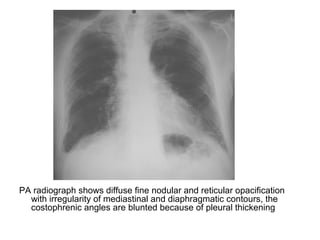

PA radiograph shows diffuse fine nodular and reticular opacification

with irregularity of mediastinal and diaphragmatic contours, the

costophrenic angles are blunted because of pleural thickening